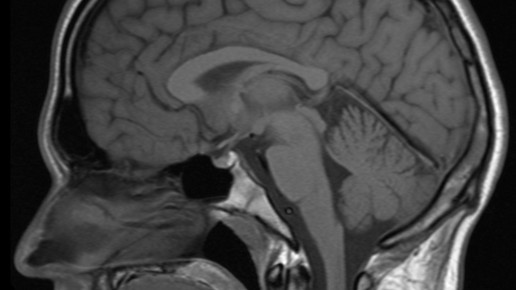

Gadolinium-haltige Kontrastmittel können für eine bessere Bildgebung während einer Kernspintomographie (MRT) eingesetzt werden. Hinweise über Ablagerungen kleiner Wirkstoffmengen im Gehirn könnten nun zu einem Ruhen der Zulassungen führen.

Dass es zu Ablagerungen im Gehirn kommen kann, hatten Studien ergeben, bei denen Gadolinium im Hirngewebe direkt gemessen wurde und auf MRT-Bildern sichtbar war. Die Gabe des Kontrastmittels lag bereits viele Monate zurück.